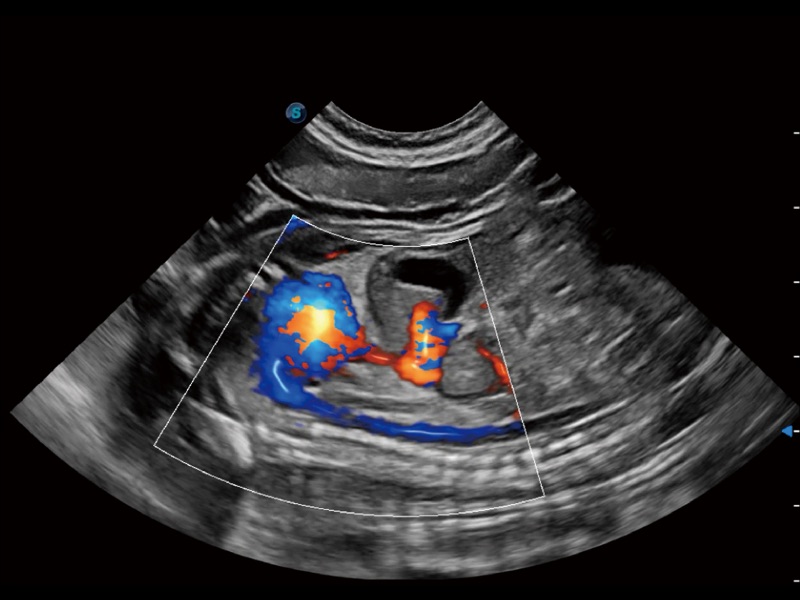

通過創(chuàng)新的 Matrix E自適應(yīng)濾波器和超長時(shí)間域算法,極大提升超低速微細(xì)血流的檢出能力,同時(shí)更精準(zhǔn)地濾除軟組織和噪聲信號,為獸用醫(yī)生提供以往無法通過常規(guī)血流獲得的疾病診斷信息。

通過色彩血流和實(shí)時(shí)寬景相結(jié)合,可觀察到完整的靜脈或動(dòng)脈的血流,方便醫(yī)生檢查。實(shí)時(shí)掃查過程中,如有任何操作失誤也可以很容易地進(jìn)行回掃擦除,而不會中斷掃查。